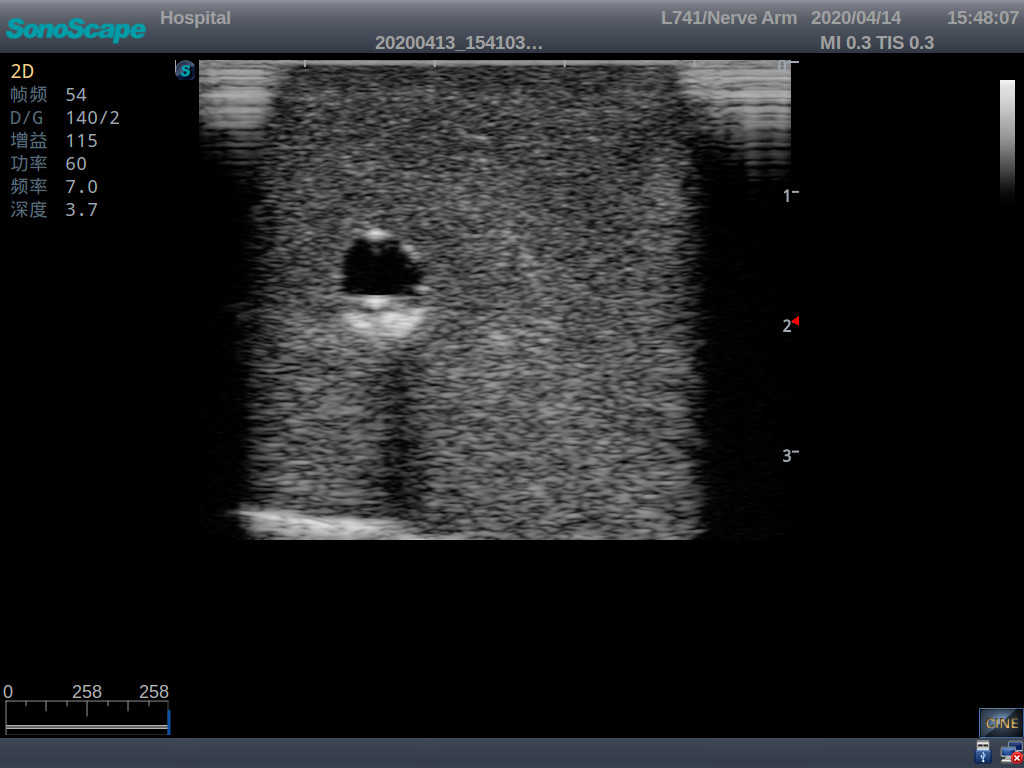

2)   It can be used by real ultrasound machines

3)   Clear and real images of the tissues and organs (basilic vein and superior vena cava)